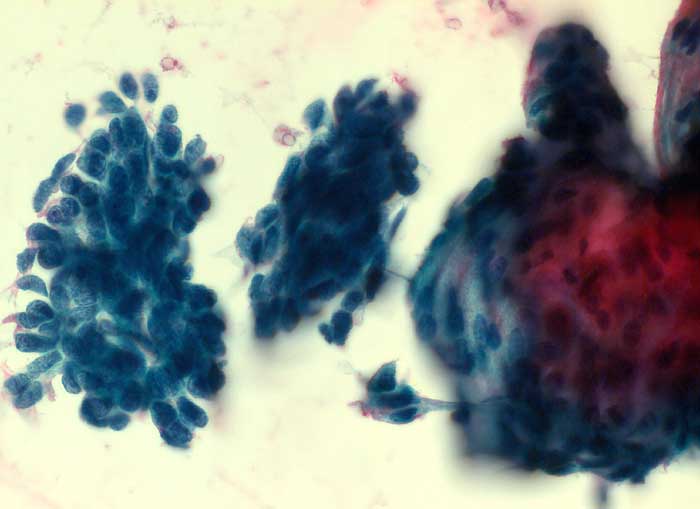

Die Tumorzellen liegen einzeln oder in kleinen Verbänden und ganzen Gewebsfragmenten. Die polymorphen Kerne sind vergrössert und enthalten verklumptes unregelmässig verteiltes Chromatin und grosse Nukleolen. Gut differenzierte Karzinome erkennt man am breiten und oft verhornten Zytoplasma. Längliche bis fadenförmige Tumorzellen mit pyknotischen Kernen können als einziger Hinweis auf das Vorliegen eines Karzinoms vorhanden sein. Wenig differenzierte Karzinome haben polymorphe und schlechter erhaltene Kerne. Der Hintergrund ist meist detritisch und oft hämorrhagisch. Ulzeration, Einblutungen und bakterielle Infektionen beeinflussen den Erhaltungszustand und die Art der abgestrichenen Zellen. Ist die Oberfläche eines ulzerierten Karzinoms von einem Fibrinschorf bedeckt, enthalten die Ausstriche lediglich Detritus, Granulozyten und Erythrozyten, aber keine Tumorzellen. Die Sensitivität für die Karzinomdiagnose ist aus diesem Grund geringer als für die Diagnose eines Carcinoma in situ.

Unten werden drei Fallbeispiele mit histologischer Korrelation gezeigt.